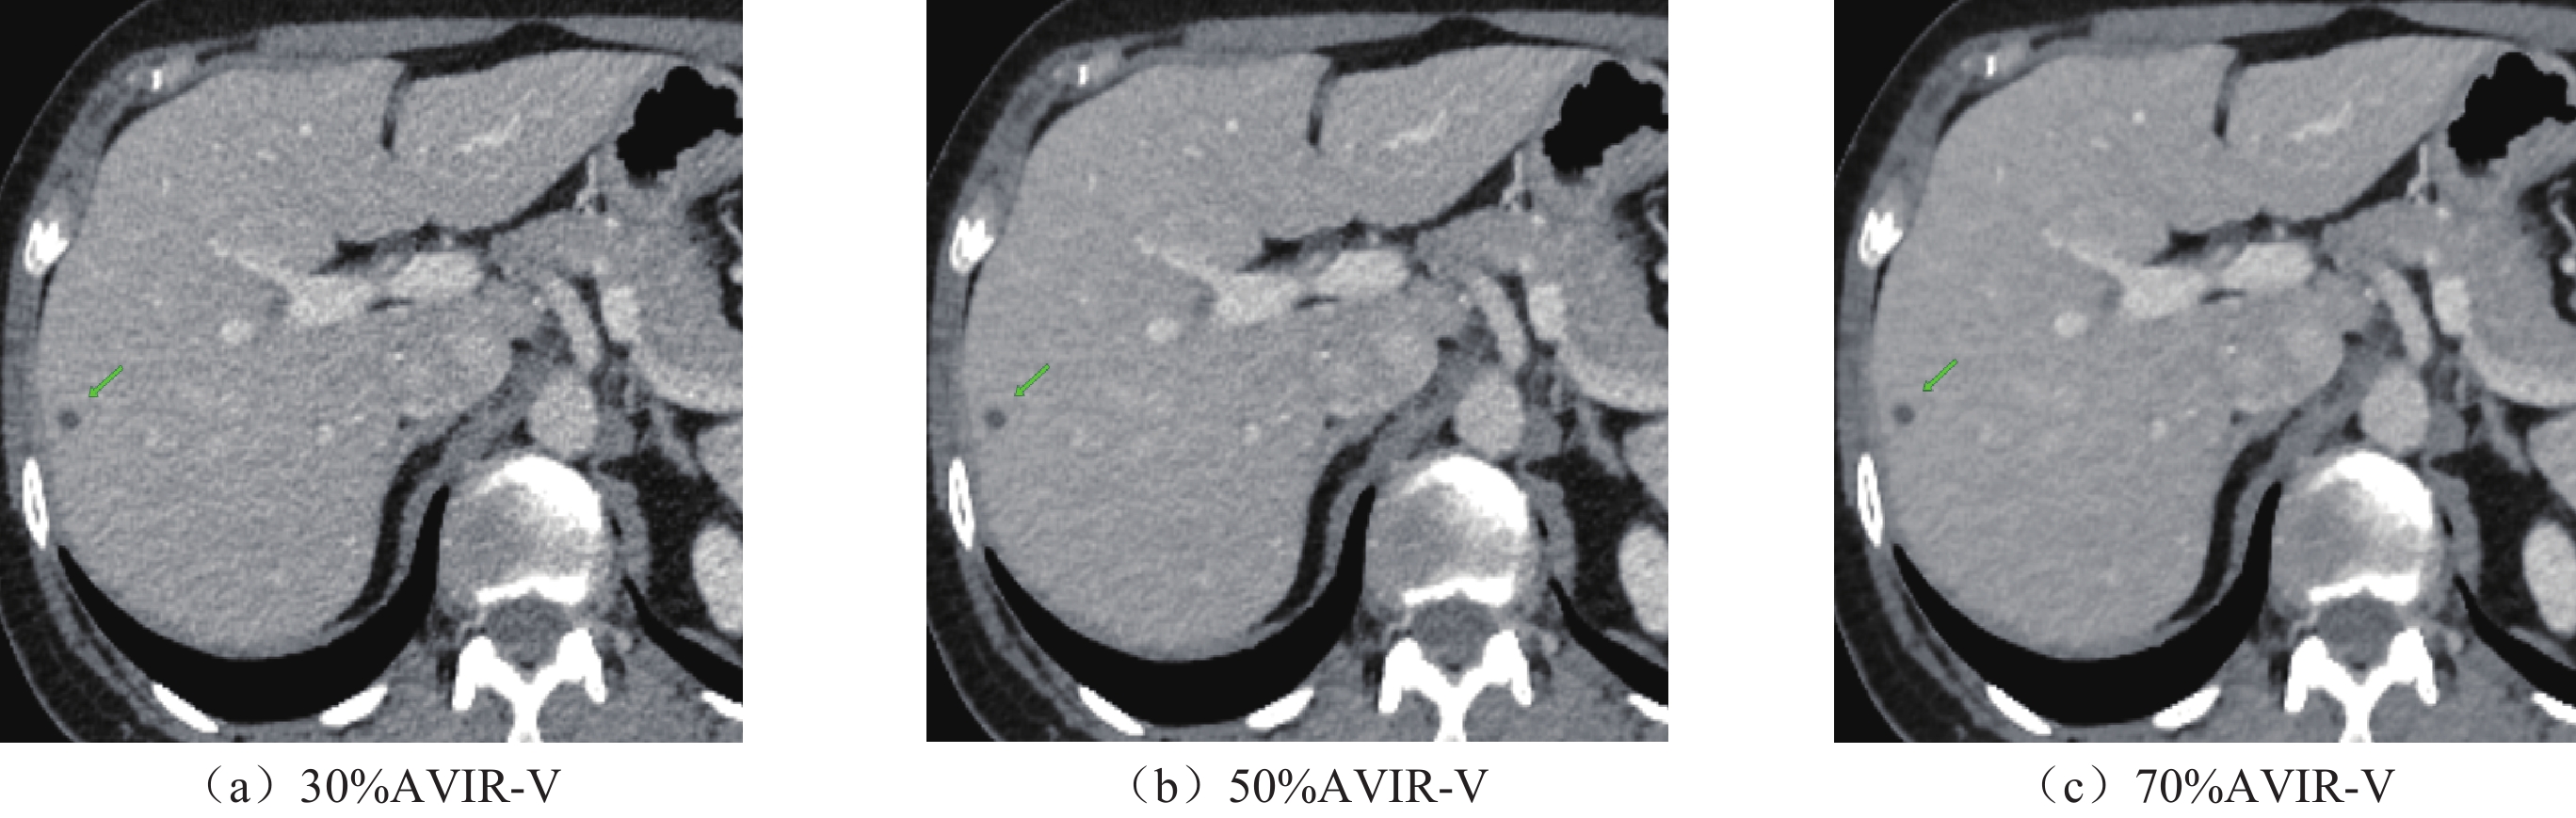

• 摘要: 目的:探讨在肝脏CT增强中结合低辐射剂量和低碘对比剂,深度学习重建算法(DLIR)与自适应统计迭代重建(ASIR-V)的应用效果。方法:前瞻性收集行腹部增强CT的患者82例,随机分成A组和B组,A组(对照组)常规剂量(管电压120kVp,碘对比剂85mL)下门静脉期采用30%、50%、70% ASIR-V(AV30、AV50、AV70)进行图像重建。B组(实验组)双低剂量(管电压80kVp;碘对比剂65 mL)下门静脉期采用中、高强度深度学习(DLIR-M,DLIR-H)进行图像重建。计算了图像噪声(SD)、信噪比(SNR)、对比噪声比(CNR)、病灶对比噪声比(LLR)、品质因数(FOM)、有效辐射剂量(ED)及碘摄入量。两名诊断医生评估不同剂量下不同重建方式的主观图像质量。结果:A组和B组的性别、年龄、体重指数BMI差异均无统计学意义。在有效剂量降低38.40%,对比剂用量降低23.53%下,DLIR-M与AV50、DLIR-H与AV70肝实质、门静脉SD值差异均无统计学意义,肝实质、门静脉SNR中仅DLIR-M与AV50不具有统计学意义,肝实质、门静脉CNR中仅DLIR-M与AV70差异无统计学意义,病灶对比噪声比(LLR)与品质因数(FOM)中,仅DLIR-M与AV70差异无统计学意义。在各项主观图像质量评估中,双低剂量下的DLIR表现优于常规剂量的AVIR-V,尤其是DLIR-H表现最佳。结论:与常规剂量下ASIR-V相比,DLIR在“双低”(低辐射剂量低对比剂)剂量下可以提高图像质量和肝脏低对比度病灶的检测能力。

Abstract: Objective: Exploration of the application of a deep-learning reconstruction algorithm (DLIR) and adaptive statistical iterative reconstruction (ASIR-V) based on the combination of low radiation dose and low iodine contrast agent in liver CT enhancement. Methods: A total of 82 patients who underwent abdominal enhanced CT were prospectively selected and randomly separated into groups A and B. Group A (control group) received a conventional dose (tube voltage 120 kVp; iodine contrast 85mL) and inferior portal image reconstruction was applied using 30%, 50%, and 70% ASIR-V (AV 30, AV 50, AV 70). In Group B (experimental group), image reconstruction was based on medium- and high-intensity deep learning (DLIR-M, DLIR-H). Image noise (SD), signal-to-noise ratio (SNR), contrast-to-noise ratio (CNR), lesion contrast-to-noise ratio (LLR), quality factor (FOM), effective radiation dose (ED), and iodine intake were calculated. Subjective image quality results were obtained for different reconstruction methods at different doses. No significant differences in gender, age, and BMI between groups A and B were found. For 38.40% effective dose and 23.53% reduction in the contrast agent dosage, no significant SD differences were found between DLIR-M and AV 50, DLIR-H and liver parenchyma and AV 70. Only DLIR-M and AV 50 in the portal SNR were not statistically significant. No significant differences were found between DLIR-M and AV 70 in liver parenchyma and portal CNR. Concerning LLR and FOM, no significant differences were found between DLIR-M and AV 70. For various subjective image quality assessments, DLIR at double low doses outperformed AVIR-V, especially DLIR-H. Conclusions: DLIR can improve image quality and the ability to detect liver low contrast lesions at “double low” (low radiation dose low contrast) compared to ASIR-V.